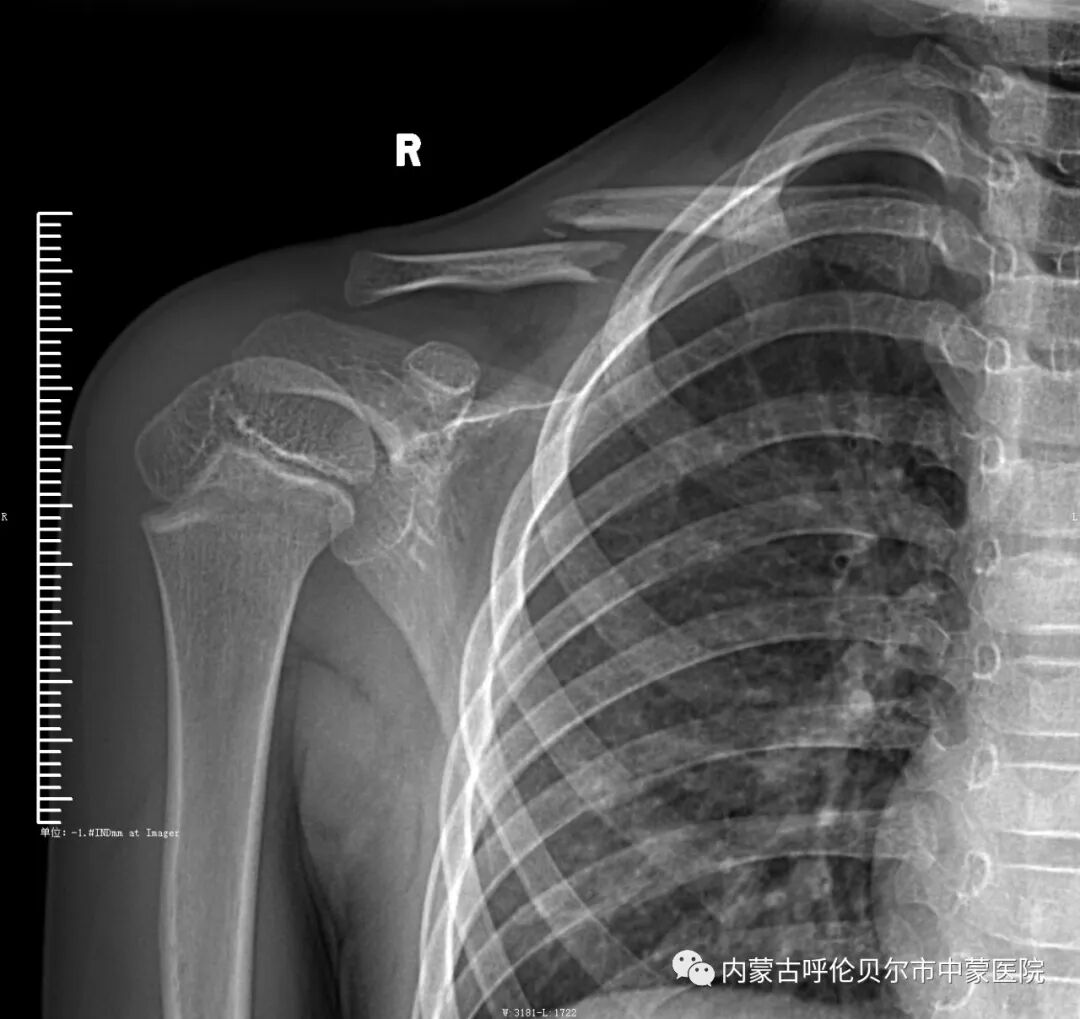

儿童2,来我院就诊前十二天摔伤,当时右侧肩部着地致右侧肩部疼痛、肿胀、活动受限,在当地行手法复位后静养,症状未见好转,遂来我院就诊,以"右侧锁骨骨折"收住院。

上述两名儿童入院后,我院骨伤科医疗团队制定和完善诊疗方案,充分进行讨论后,决定行微创手术。该项手术可以做到“零切开”,无明显瘢痕,对儿童皮肤表面无影响,不影响未来骨质发育。术后可立刻改善肩部疼痛不适症状,一个月后可取出内固定装置。该项手术可将感染几率大幅降低,早期促进儿童骨质愈合,不影响未来生长发育。